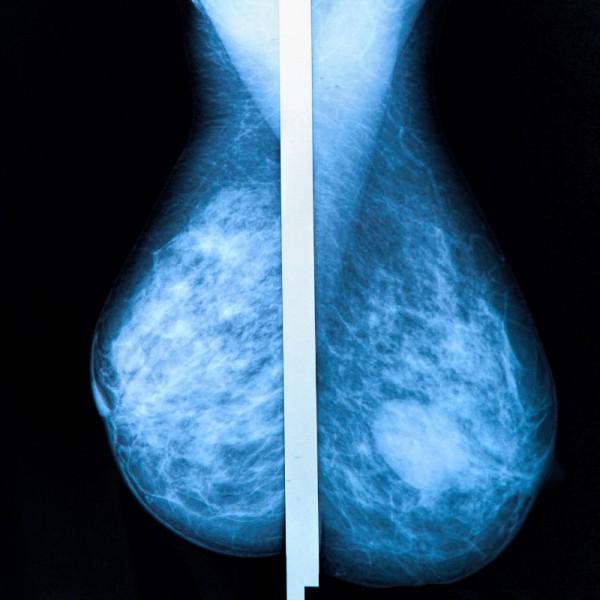

| Invita IMSS Veracruz Norte a mujeres derechohabientes a campaña de mastografías |

| .- Con el propósito prevenir o, en su caso, detectar oportunamente el cáncer de mama, el Instituto Mexicano del Seguro Social (IMSS) en Veracruz Norte invita a las mujeres derechohabientes de 40 a 69 años, a acudir a la campaña de mastografías.

"Las mastografías buscan detectar cambios o anormalidades en los tejidos del seno que con el ti... |